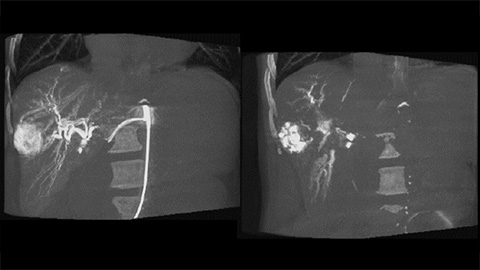

CBCT enables 3D acquisition of an arterial phase to visualize vascular structures and a post-arterial (delayed phase) to optimally visualize accumulation of contrast medium, in a single automatic step [3].

Dual View allows simultaneous visualization of two CBCT datasets (pre and post). Both arterial and delayed phase can be displayed next to each other or in a single fused overlay view.

Dual View allows simultaneous visualization of pre-embolization arterial phase 3D image and the post embolization image to assess treatment endpoint and predict outcome.